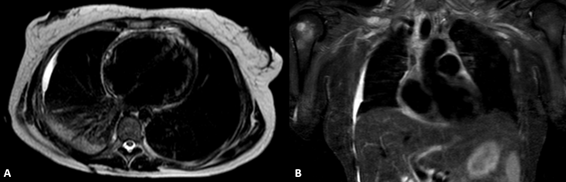

Figure 3 Total-body MRI confirming the resolution of the pericardial effusion and no evidence of endocardial tumors.